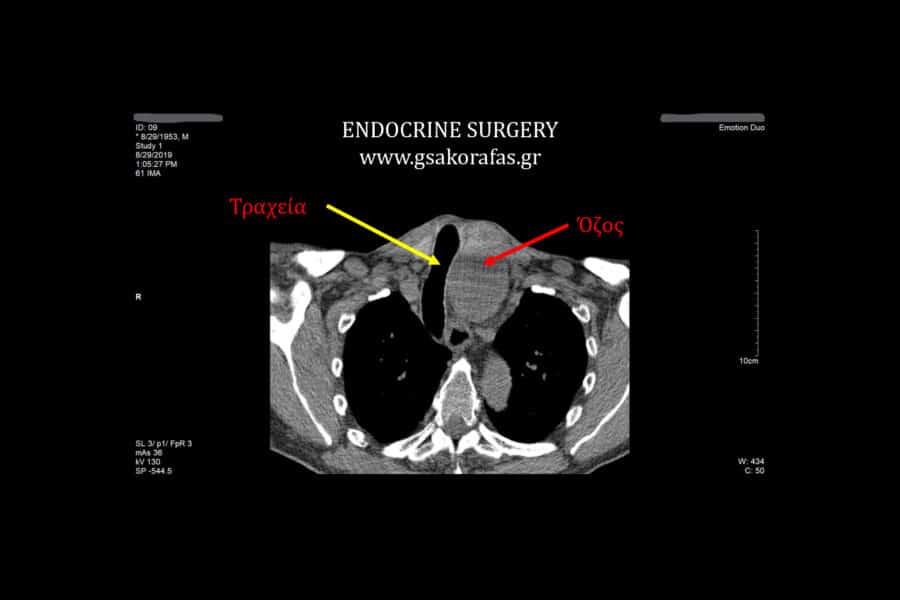

Γιγάντια καταδυόμενη βρογχοκήλη σε υπερήλικα ασθενή μας: ασφαλής θυρεοειδεκτομή με 1 ημέρα νοσηλεία.

Γιγάντια καταδυόμενη βρογχοκήλη σε υπερήλικα ασθενή μας: ασφαλής θυρεοειδεκτομή με 1 ημέρα νοσηλεία Εισαγωγή Υπερήλικας…